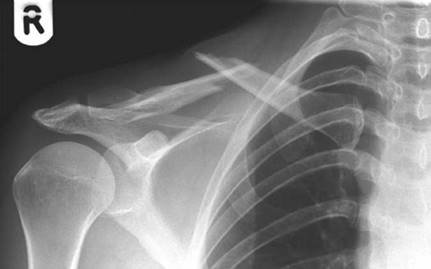

This is an AP radiograph of the left shoulder showing an antero-inferior dislocation of the shoulder. One should look for associated injuries including greater tuberosity fractures, bony Bankart lesions and glenoid fractures.

Complications of anterior dislocation include axillary nerve palsy (5โ30 % ), rotator cuff tear (14โ63 % , increased in elderly), greater tuberosity (GT)/glenoid rim fracture ( > 20 % , = fi xation).

S tructures that may block reduction would include buttonholing through the capsule, biceps tendon, or bony fragments.